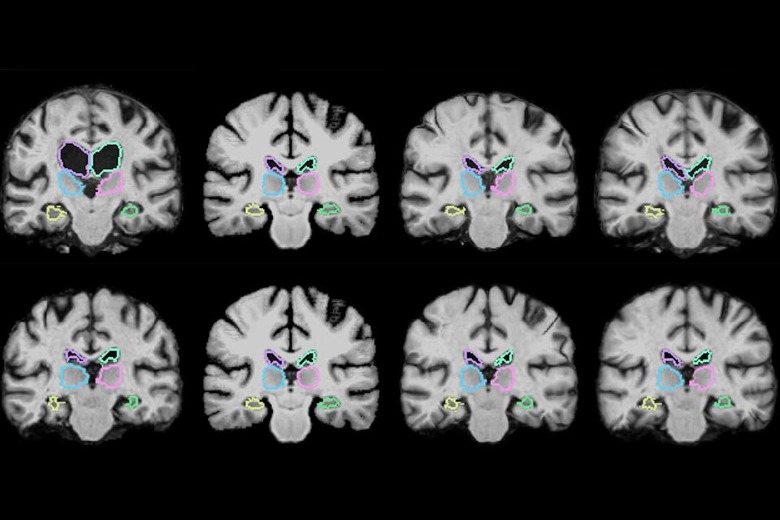

Right now, comparing 3D medical scans is a pain — it can take two hours or more to see what's changed. And that spells trouble for surgeons, who may have to bring patients back to the operating room if a tumor removal wasn't a complete success. Thankfully, AI technology may eliminate that hassle. An MIT-led research team has crafted a machine learning algorithm that can analyze 3D scans up to 1,000 times faster than before, making it possible to study changes almost in real time — less than a second on a PC with a fast graphics card.

The approach starts by training the algorithm on "thousands" of image pairs, teaching it how to align the scans and provide meaningful comparisons. After that, it can map every voxel (3D pixel) of both scans at the same time. That's no mean feat when there are frequently a million voxels between the two pictures. Existing systems start fresh with every new image, effectively forgetting everything they learned about location from the last time around.